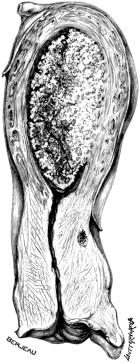

| 5. | Primary Cancer of the Fallopian Tube | 27 |

| 6. | A Section of Primary Cancer of the Fallopian Tube | 27 |